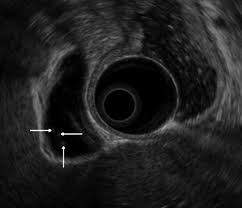

I just didn't feel right. I was like that for a month and a half. If they're swollen, the lymph nodes may feel like smooth lumps under the skin. Esophageal cancer causes food to get stuck or feel like it's sticking in the esophagus. Stomach cancer is usually asymptomatic early on, or causes vague symptoms like bloating, indigestion, and a feeling of fullness in the upper abdomen.

Or the cancer could release substances that change the way the body makes energy. He is 6 months cancer free right now. Understandably, this can terrify women. Your stomach receives and holds the food you eat and then helps to break down and digest it. In its early stages, lung cancer doesn't typically have symptoms you can see or feel. It really is a great app and makes me feel like i am in the room with my folks. Some women report feeling a pulse in their stomach when they're pregnant.while this might feel like your baby's heartbeat, it's actually just the pulse in your abdominal aorta. But for many sufferers, pain is not among the early warning signs of stomach cancer. About half of soft tissue sarcomas start in an arm or leg. I suddenly became nauseated, rapidly losing weight, constipated, and felt awful. I don't have a family history of colon cancer. I'm dying of stage 4 stomach cancer. I just didn't feel right.

Image if you have stomach cancer within what does stomach cancer feel like article related to what does stomach cancer feel like : I just didn't feel right. Some patients describe pain starting in the middle abdomen and radiating into the back. I'd bloat, get an upset stomach and i had acid reflux. Later, it often causes coughing, wheezing, and chest pain.

Stomach cancer, also known as gastric cancer, can affect any part of the stomach. He also had a problem with bleeding gums as he grinds his teeth at night, this is apparently a sign of some kind of kidney disease. On the way to the ct scan he ordered, i told my husband, 'this must be what cancer feels like, i'm in so much pain.' the scan showed a shadow on her liver. I'm dying of stage 4 stomach cancer. Unlike many young women, however, my ibs. Lymph nodes are collections of immune system cells. The cancer may now be in all layers of the stomach, as well as other organs close by, like the spleen or colon. Eva katalin kondoros / getty images. Pancreatic cancer is a tricky cancer to identify. Like pancreatic cancer, it may have already. Understandably, this can terrify women. In some cases the tumor may be pressing on a nerve, causing a constant burning pain. Had a ct, mri, bloods and ogd.